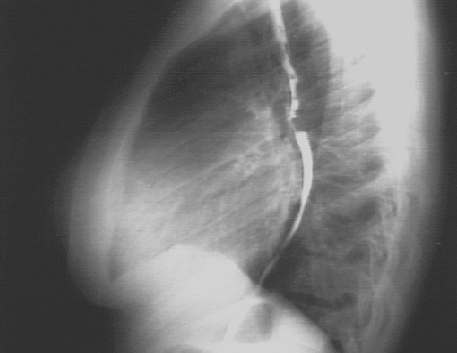

The markedly enlarged left atrium is manifested by the double contour within the heart border, an elevated left mainstem bronchus, and an enlarged left atrial appendage. The lateral view with barium swallow, demonstrates posterior displacement of the esophagus by the markedly enlarged left atrium.